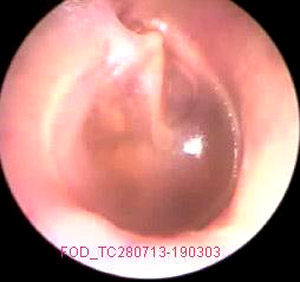

JFC Otitis media serosa

JFC Otitis media serosa.

JFC Otitis media serosa de origen disbárico.

JFC Otitis media serosa izquierda.